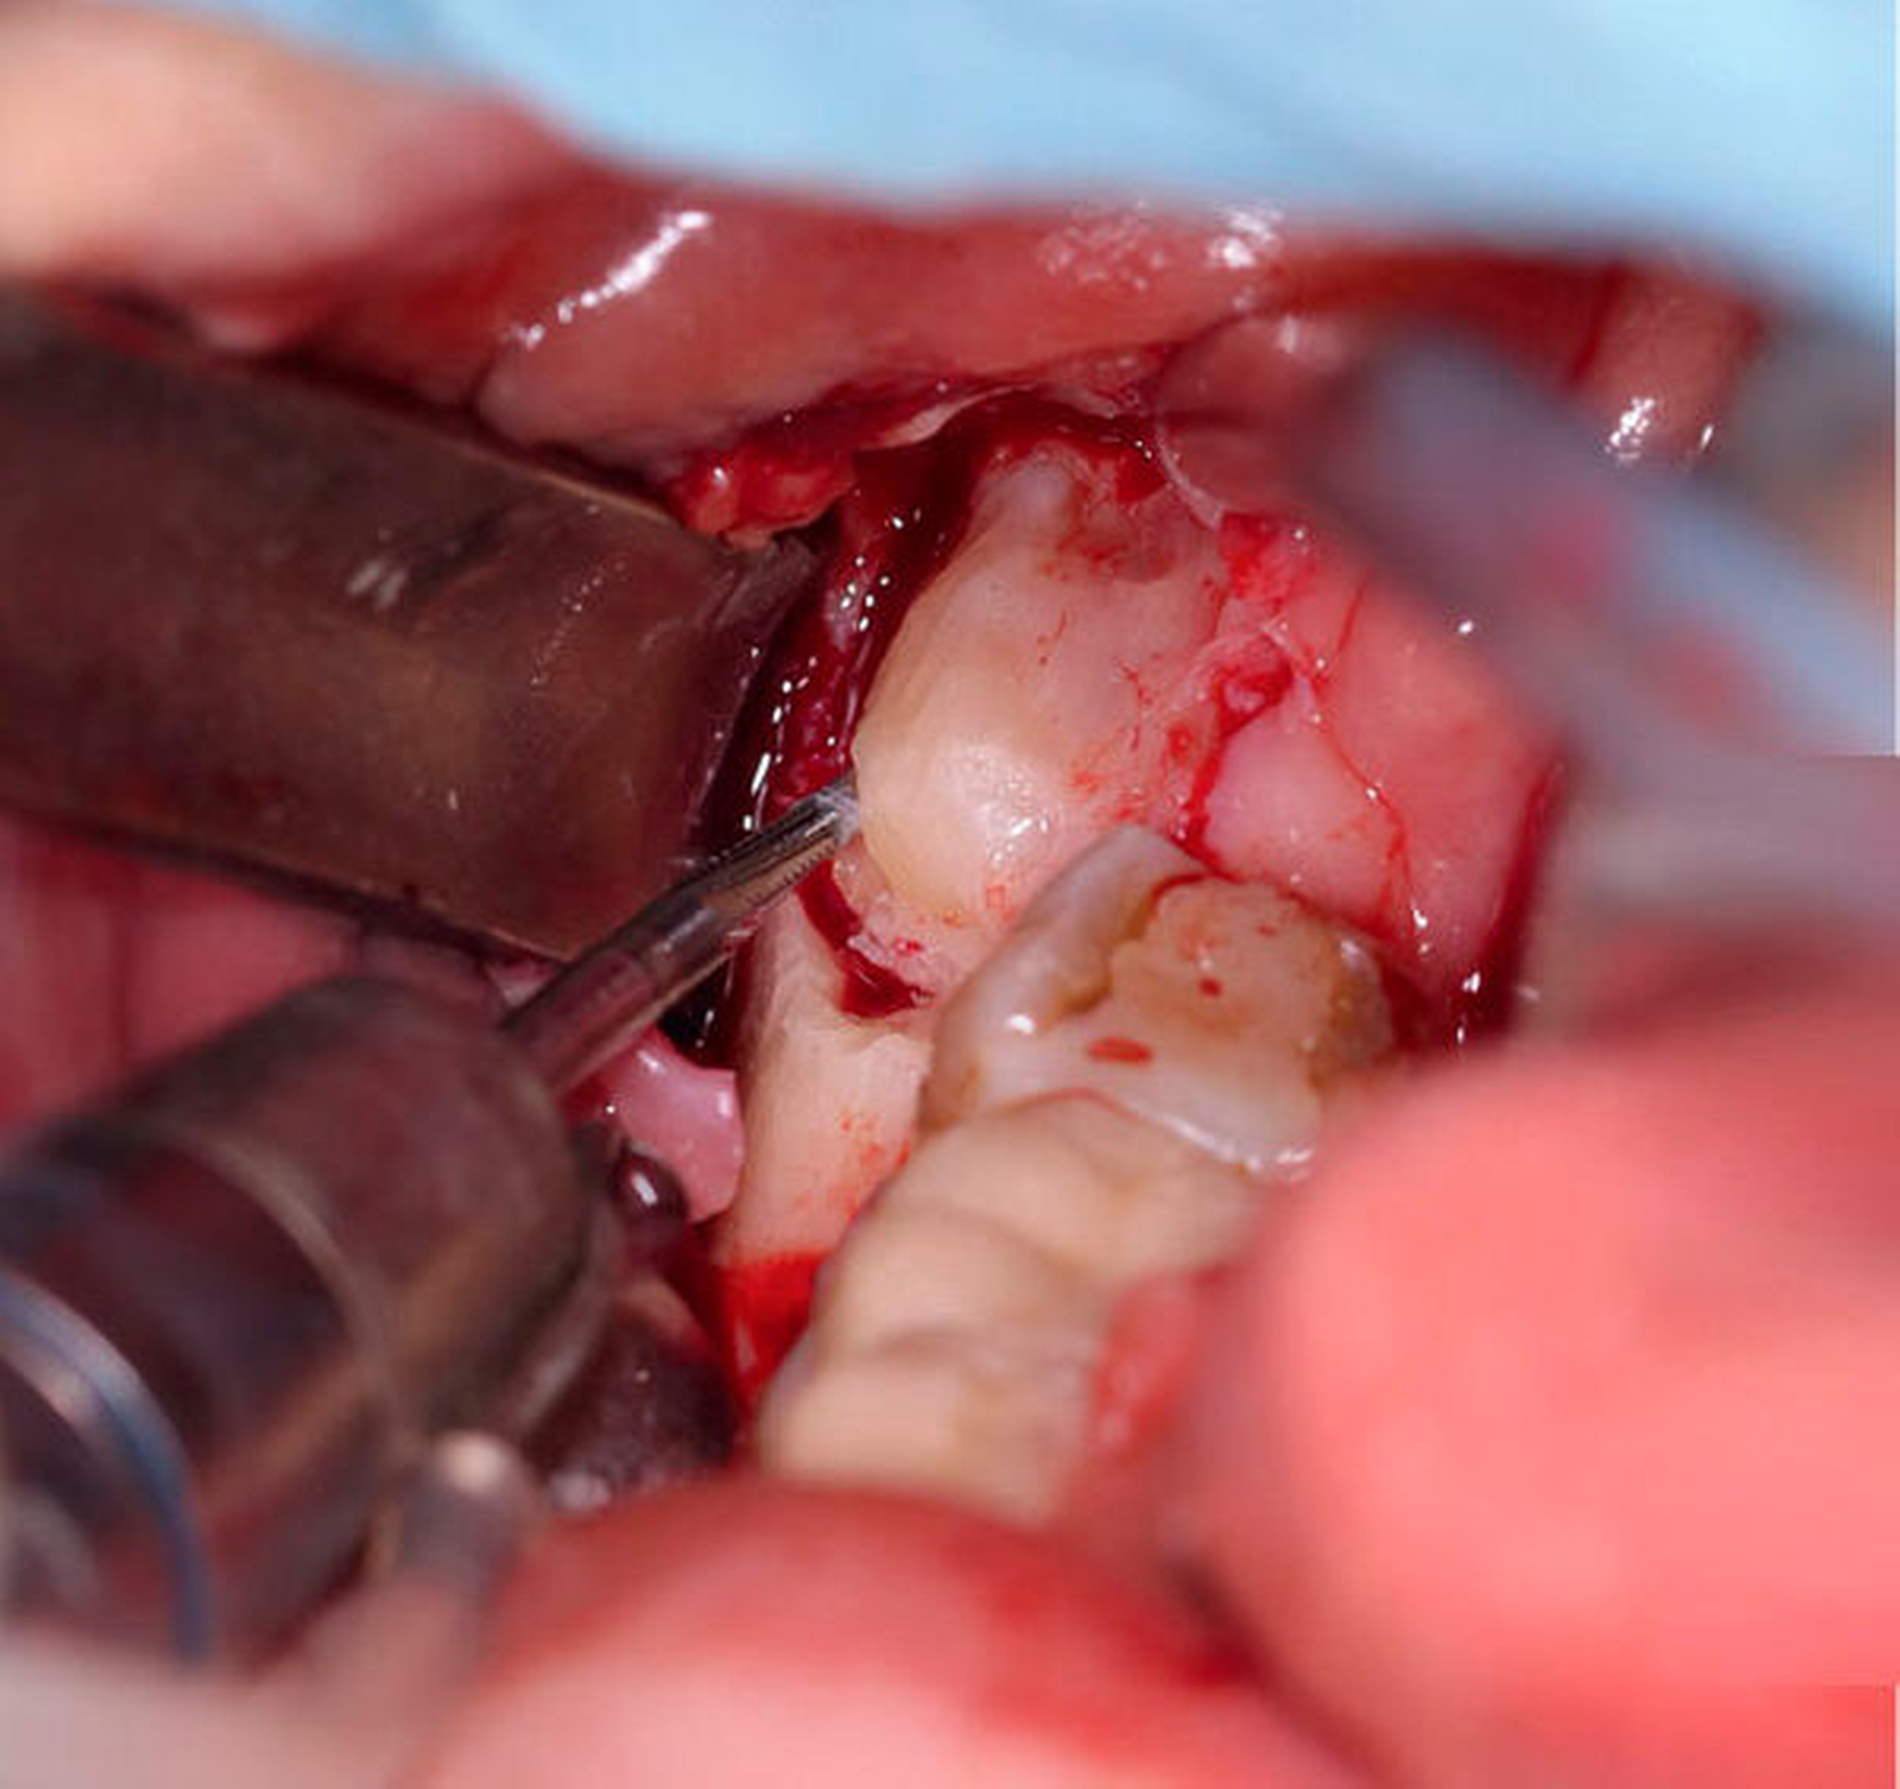

Wir entschieden uns zunächst für die klassische operative Entfernung der Zähne 28 und 38. Aufgrund des Risikos einer Nervschädigung bei der Entfernung des Zahnes 48 wurde zudem eine Koronektomie des Zahns in ambulanter Intubationsnarkose beschlossen. In Regio 48 wurde nach Schnittführung von retromolar nach distal 47 mit vestibulärer Entlastung und Bildung eines Mukoperiostlappens der Zahn 48 freigelegt (Abbildung 4). Die Zahnkrone konnte komplikationslos abgetrennt werden, woraufhin die Glättung des Wurzelblocks bei guter Sicht möglich war (Abbildung 5). Dabei wurde streng darauf geachtet, alle Schmelzanteile resektiv zu entfernen. Anschließend wurden die Wundflächen gereinigt und die Wunde durch Nähte verschlossen. Der postoperative Verlauf war unauffällig und die Patientin wurde am gleichen Tag in die ambulante Nachsorge entlassen. Zur Entzündungsprophylaxe erhielt sie Schmerzmittel. Des Weiteren wurde ihr geraten, eine starke Kaubelastung zu vermeiden.